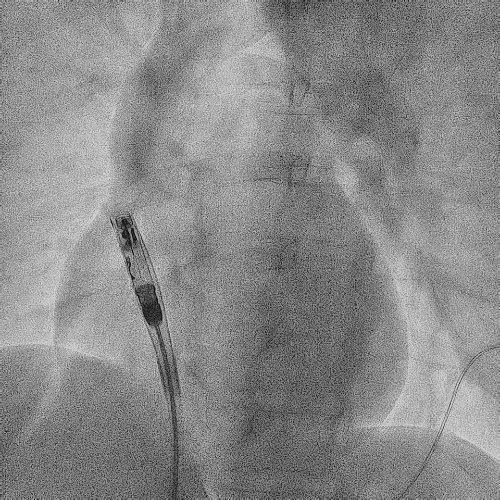

电极拔除

打开囊袋取出原起搏器后,使用锁定钢丝锁定分别锁定两根导线,备用激光鞘并未使用。直接徒手顺利拔除两根导线。

电极拔除过程